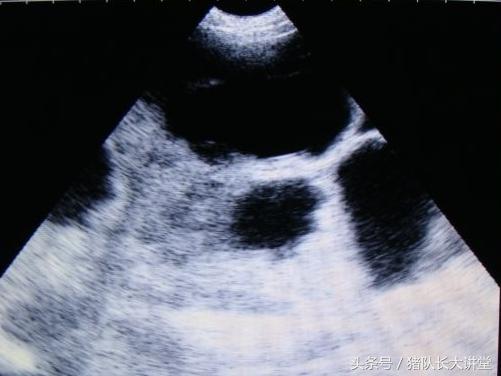

中间的黑球是初期胚胎